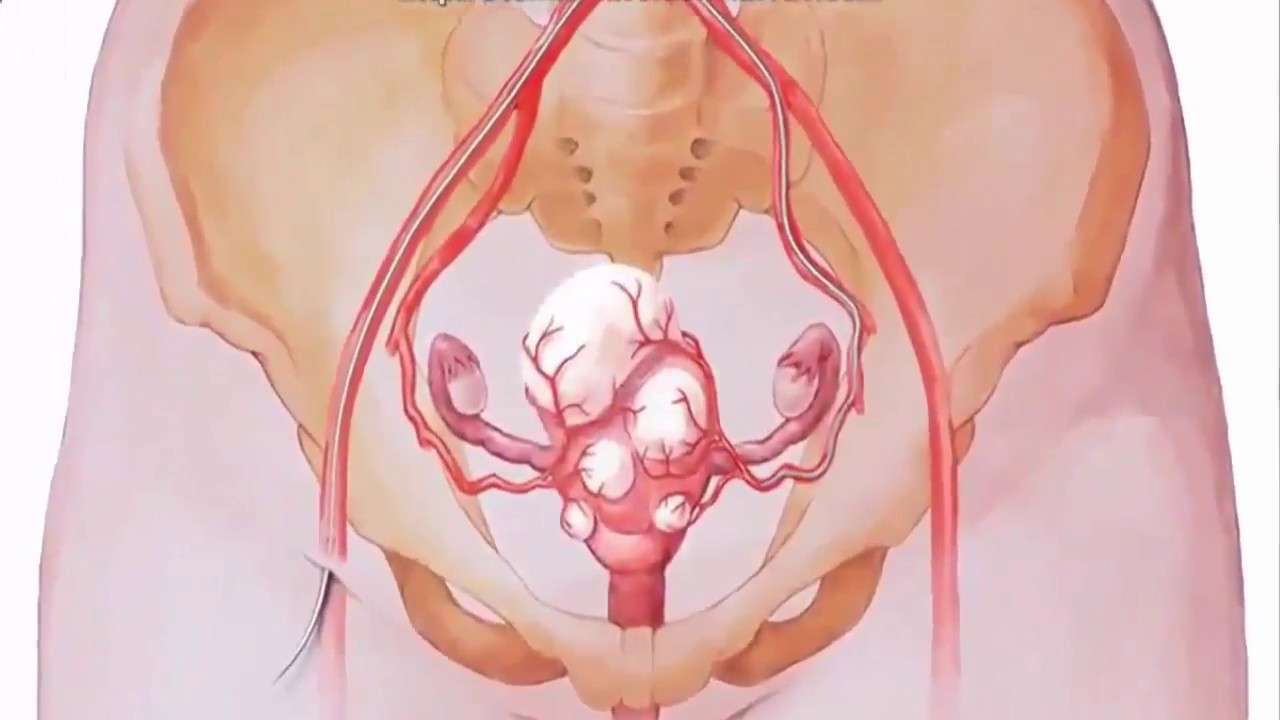

Боль в малом тазу у женщин: Причины и подходы к лечению